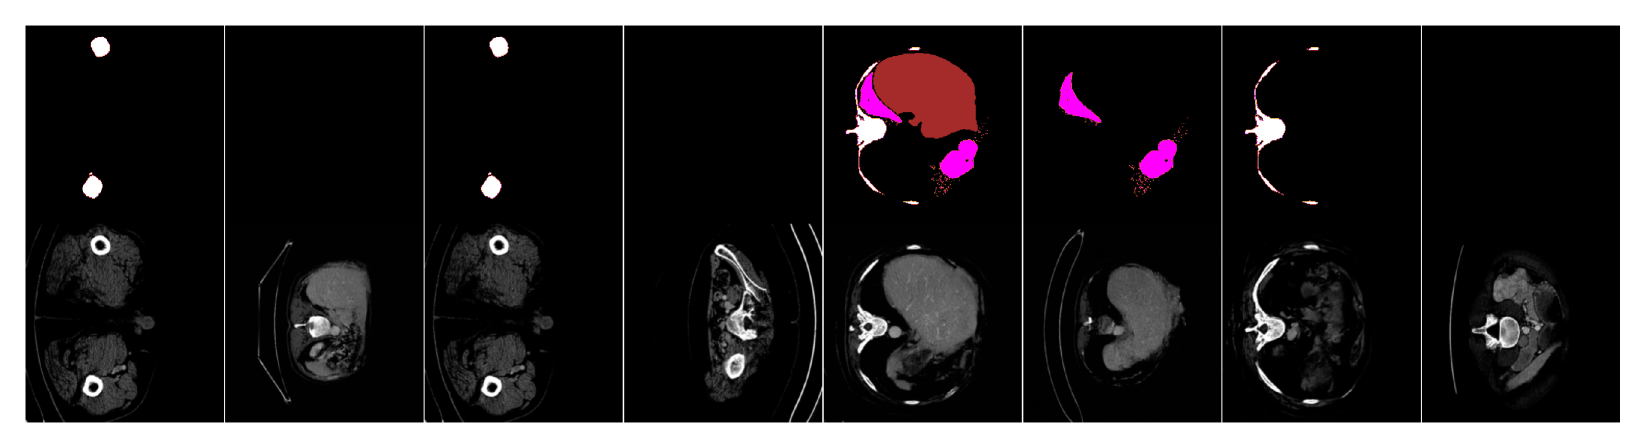

We show additional samples for both datasets for all models in Fig. LABEL:fig:samples_many (to supplement Fig. LABEL:fig:samples). Similarly, we show more samples with various classes removed from input masks to illustrate the effect of mask-ablated training (Sec. 1.3) in Figures LABEL:fig:samples_many_abla_breast and LABEL:fig:samples_many_abla_ct for breast MRI and CT organ, respectively, to supplement Fig. LABEL:fig:samples_ablated.

fig:samples_many

fig:samples_many_abla_breast

fig:samples_many_abla_ct